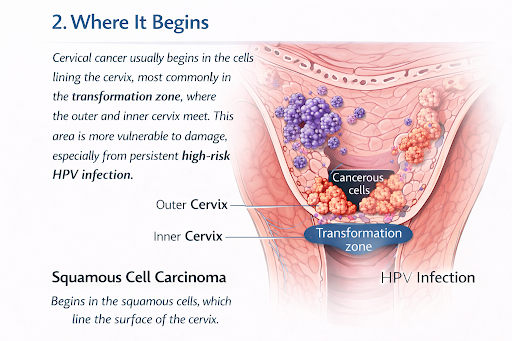

2. Where It Begins +

Cervical cancer usually begins in the cells lining the cervix, most commonly in the transformation zone, where the outer and inner cervix meet. This area is more vulnerable to damage, especially from persistent high-risk HPV infection.